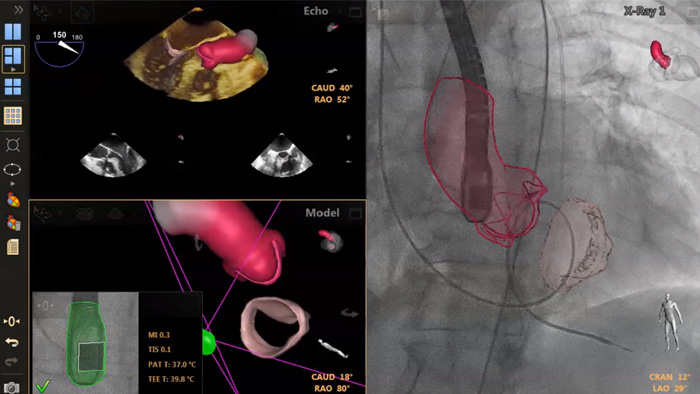

En el centro de nuestra suite, la exclusiva solución EchoNavigator es el ejemplo emblemático del compromiso de Philips con la multimodalidad y la integración del flujo de trabajo, aporta lo mejor de ambos mundos del líder de la industria en soluciones cardíacas intervencionistas de rayos X y ecografía.

Visualización de la reparación mitral de la regurgitación posimplante

Visualización TrueVue de la valvulopatía mitral de extremo a extremo

Visualización de las válvulas mitral y aórtica con modelos cardíacos EchoNavigator